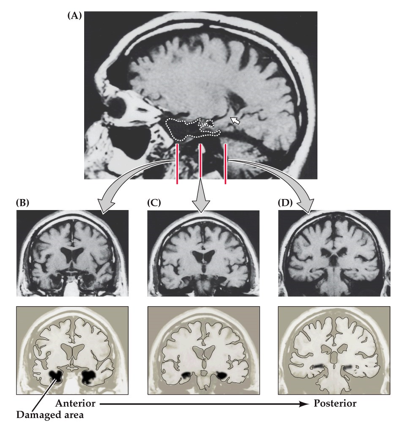

In epileptic patients, they can remove parts of the hippocampus to treat symptoms. In order to do this, surgeons need to cut away a piece of their temporal lobe. This can be used for research. With this, they also performed cognitive and mental tests (see picture).

It’s seen that:

• cortical thickness predicts dendrite length.

• cortical thickness positively correlates with IQ

• the speed of action potentials during repeated firing is faster in subjects with a high IQ

Note: these are correlational studies